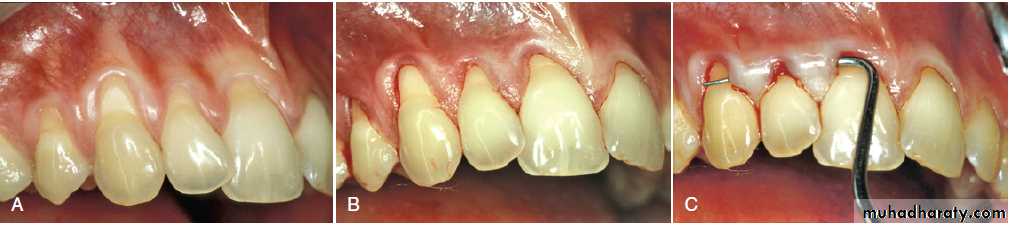

(A) Pretreatment recession defect of 3 mm to be treated with enamel matrix derivative (EMD). (B) Application of EMD to the root surface before coronally advancing the flap with 5-0 plain gut sutures. (C) The 1-year follow-up reveals 100% root coverage and increased keratinized gingiva.